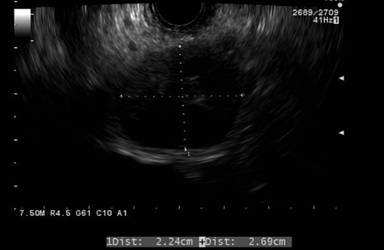

A 50-year-old man undergoing staging evaluation for multiple myeloma was referred for EUS evaluation of a pancreatic head mass seen on abdominal CT scan (Figure 1). EUS confirmed an approximate 26.9x22.4 mm mostly hypoechoic solid mass process with smaller anechoic spaces suggestive of cystic component involving the pancreatic head and adjacent porta hepatis region (Figure 2). EUS-FNA was performed with a 25-gauge needle (Cook Medical, Bloomington, IN, USA). A total of four trans-duodenal passes were taken without complication (Figure 3). Antibiotic prophylaxis to prevent infection was provided due to possible cystic component. Cytopathology revealed abundant amorphous acellular waxy appearing proteinaceous deposits (Figure 4). Congo red staining of these deposits demonstrated apple-green birefringence under polarized light indicative of amyloid (Figure 5). The patient underwent subsequent autologous stem cell transplantation for treatment of myeloma with subsequent resolution of the pancreatic process.

Figure 2. EUS image showing pancreatic head process (linear echoendoscope at 7.5MHz). |